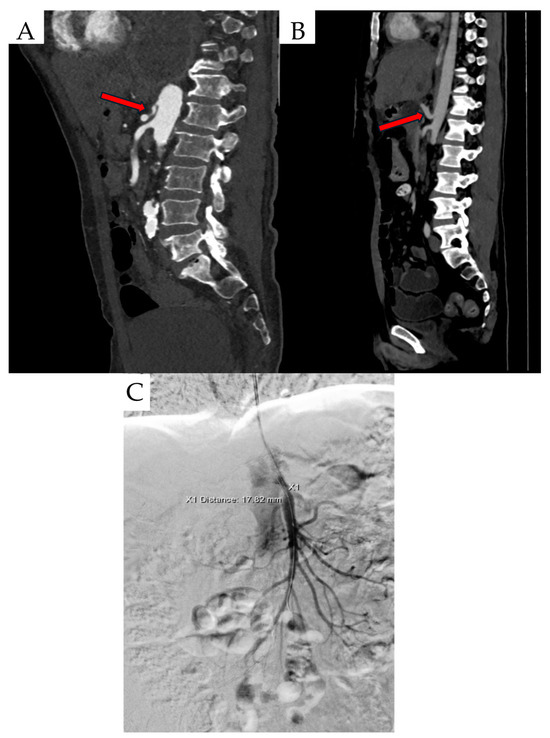

Another diagnostic modality used to evaluate patients with suspected MALS is CTA, which allows for meticulous assessment of celiac trunk and MAL anatomy. Some of the MALS characteristics in CTA scan include inferior displacement of the celiac trunk, proximal compression of celiac artery, MAL thickening, Angio CT on inspiration and expiration, celiac artery stenosis and “hook sign” (Figure 1) [37]. To date, MAL thickening has been considered significant when thickness is greater than 4 mm. However, recent studies indicate a mean MAL thickness at CTA in men and women of 8.4 ± 2.52 mm and 6.9 ± 2.41 mm, respectively. In addition, the mean distance of the MAL from the CT was 1.32 ± 2.04 mm, and the most common angle of celiac trunk exit was the obtuse angle, which is consistent with adaptation to compression [38,39]. Interestingly, in a study by Ganapathy et al. there was no significant correlation between anatomic measurements such as CA angle, CA diameter, thickness of MAL and MALS symptoms such as pain, weight loss, nausea, vomiting [38]. Therefore, diagnosis should be based not only on the assessment of the thickness of the MAL, but also the distance of the CT from the MAL, the determination of the angle of departure of the CT, the presence of post-stenotic CT dilatation and the assessment of the dynamics of flow through the celiac trunk on inspiration and expiration [39]. “Hook sign” is defined as focal narrowing in the proximal celiac artery and is useful in differentiating MALS from other pathologies [40]. Chan et al. characterized “hook sign” in their study as a fold angle of CA lower than 135°. MALS patients in comparison with non-MALS patients had significantly more severe fold angle of CA in CTA scan (p=0,002) [41]. “Hook sign” in CTA scan had the sensitivity of 71% and specificity of 59%. CE-MRA can be considered as a potential alternative to CTA in patients who should avoid exposure to radiation or have allergy for contrast used in CTA [4].

Figure 1.

Created based on unpublished clinical data from Department of Vascular Surgery and Angiology, Pomeranian Medical University in Szczecin. (A) CTA findings include inferior displacement of the CT by proximal celiac artery compression. (B) Celiac artery stenosis and ‘hook’ sign (red arrows). (C) Digital subtractive angiography (DSA) scan in a patient with MALS.